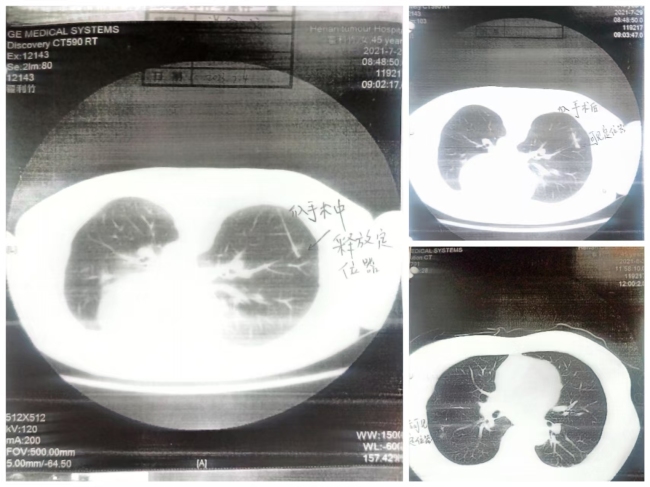

在术前检查中,意外发现右肺上下叶各有一个结节。

基于胸外科医生的建议,翟女士接受了切除手术,被告知结节为炎性病变,并已成功切除。

然而,在术后复查时,翟女士惊讶地发现自己肺部的结节并未被切除,且一年后确认这两个结节均为恶性肿瘤。

进一步调查发现,手术过程中定位针“失踪”,导致未能准确切除目标结节,而医生凭经验用手触摸切除了一个疑似结节,事后证实该组织并非预期的目标结节。